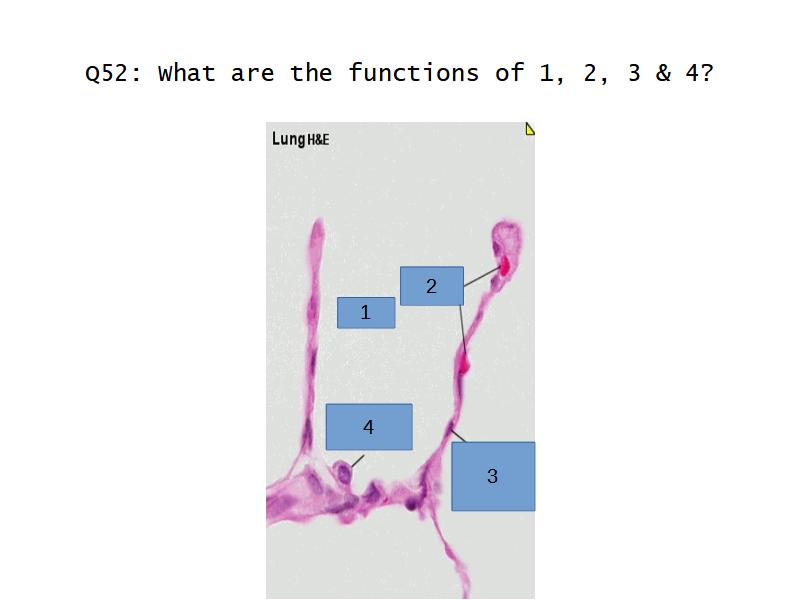

What cells are present?

Components of the Blood-Air Barrier?

- Alveoli